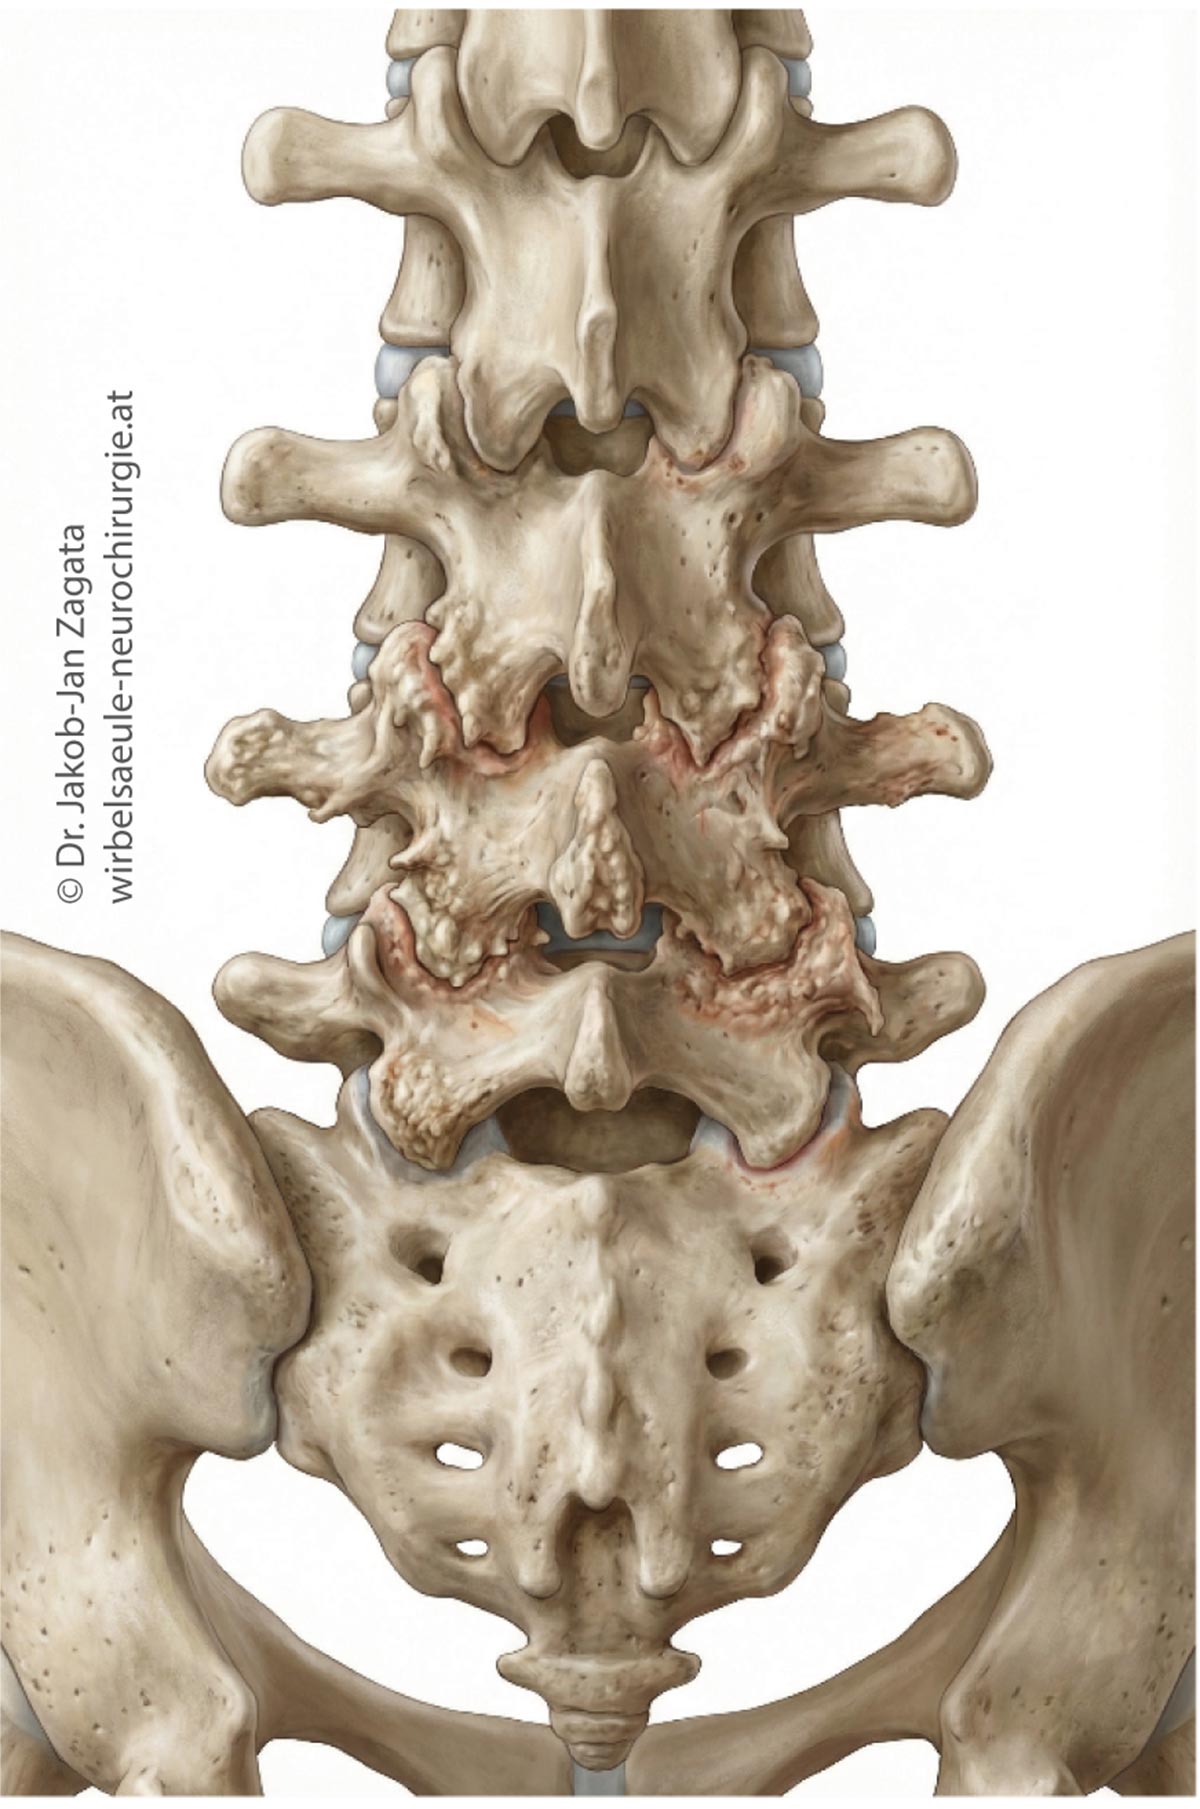

Chronische Kreuzschmerzen zählen zu den häufigsten Beschwerden im Bereich der Wirbelsäule. In vielen Fällen liegen ihnen degenerative Veränderungen zugrunde, die im Rahmen des natürlichen Alterungsprozesses entstehen und unterschiedliche Strukturen der Wirbelsäule betreffen können. Dazu zählen insbesondere die Spondylose, die Osteochondrose sowie die Facettengelenksarthrose.

Die Spondylose beschreibt degenerative Veränderungen der Wirbelkörper und Bandscheibenränder, häufig mit knöchernen Anbauten. Bei der Osteochondrose kommt es zu Abnützungserscheinungen der Bandscheiben und angrenzenden Wirbelkörper, während die Facettengelenksarthrose die kleinen Wirbelgelenke betrifft. Diese Veränderungen können einzeln oder kombiniert auftreten und zu einer mechanischen Überlastung sowie Schmerzhaftigkeit der Wirbelsäule führen.

Klinisch äußern sich diese Erkrankungen häufig durch anhaltende oder belastungsabhängige Kreuzschmerzen, morgendliche Steifigkeit, Bewegungseinschränkungen oder ein lokales Schmerzempfinden. In manchen Fällen können die Beschwerden in Gesäß oder Beine ausstrahlen, ohne dass eine eindeutige Nervenkompression vorliegt.